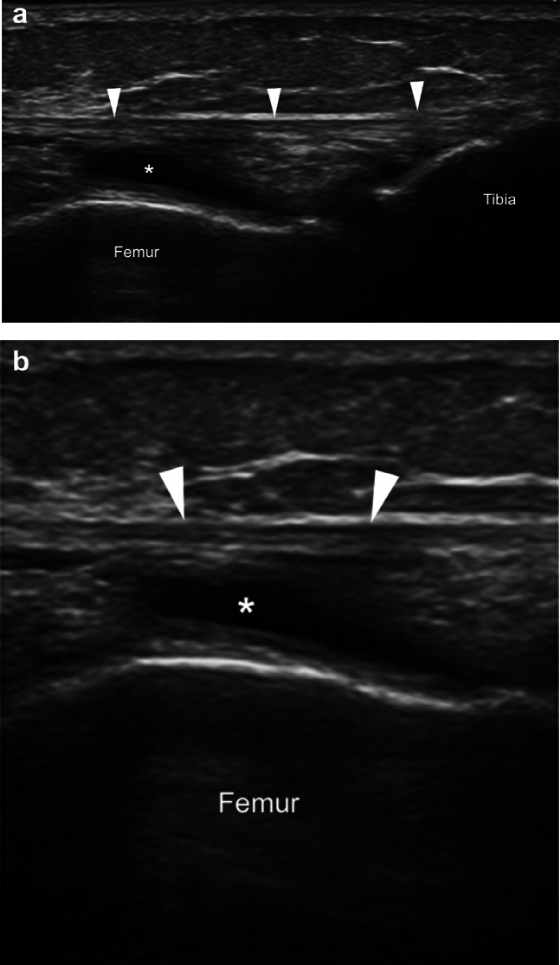

髂胫束综合征或摩擦综合征是膝关节外侧过度使用的疾病。它在运动员(例如跑步和自行车)群体中高发。超声影像作为一种高性价比的成像方式,能够以高分辨率、动态评估以及与对侧健康侧进行比较来显示浅表软组织结构,对于评估髂胫束综合征具有重要参考价值。

- 关于第一点的“摩擦说”:与髂胫束在涉及重复膝关节屈伸的活动中来回摩擦股骨外上髁有关,从而导致髂胫束摩擦和邻近软组织发炎。多年来,这一病因一直存在争议,特别是关于髂胫束运动的方向和程度。然而,一项超声研究表明,在膝关节伸展和屈曲期间,髂胫束相对于股骨外上髁沿前后方向移动,因此支持摩擦作为病因学因素的核心作用。